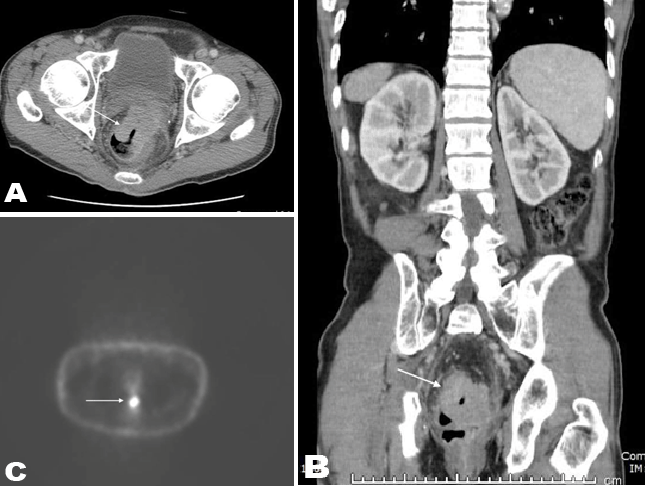

A 56-year-old male with recently diagnosed rectal cancer presented in the emergency department with recurrent seizures and disorientation for some days. Magnetic resonance imaging scan of brain demonstrated hyperintense signal on T2- FLAIR image (Figure 1A) and restricted diffusion on diffusion weighted image (Figure 1B) in right medial temporal lobe. There was no enhancement after contrast administration (Figure 1C). Patient's initial computed tomography (CT) scan of the abdomen and pelvis (Figure 2A-B), and positron emission tomography (PET) scan (Figure 2C) showed the presence of a large rectal mass with intense metabolic uptake. Based on clinical history and imaging findings, diagnosis of PLE was suggested. Serologic investigation showed a highly positive titer for anti-Ri (1:2560, normal <80). Subsequent cerebrospinal fluid analysis also showed increased titers of anti-Ri antibody with no findings to suggest viral or bacterial encephalitis. Since patient was already on chemotherapy treatment for rectal cancer, antiepileptic therapy and steroid treatment were also started. In next few days, the patient was free from seizure episodes and the neurological symptoms gradually improved. Follow-up MRI scan of brain was showed complete interval resolution of the abnormalities (Figure 3A-C).

Figure 2: (A) Axial and (B) coronal contrast enhanced CT demonstrating presence of a large rectal mass. (C) FDG-PET image showing intense metabolic uptake in the region of rectal mass.